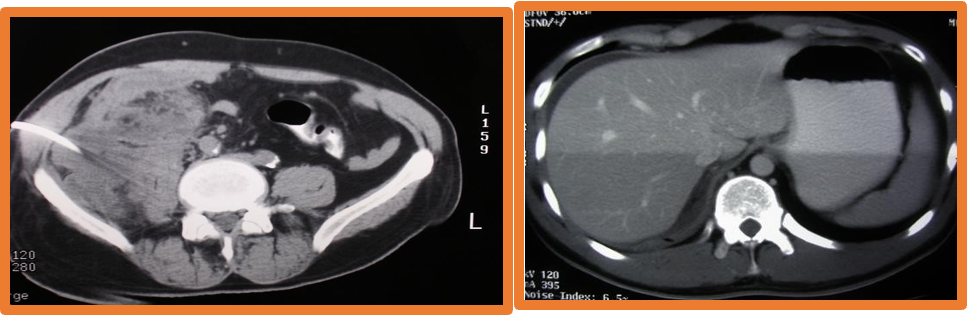

- Imaging:, AXR, Ultrasound, CT scan-most helpful